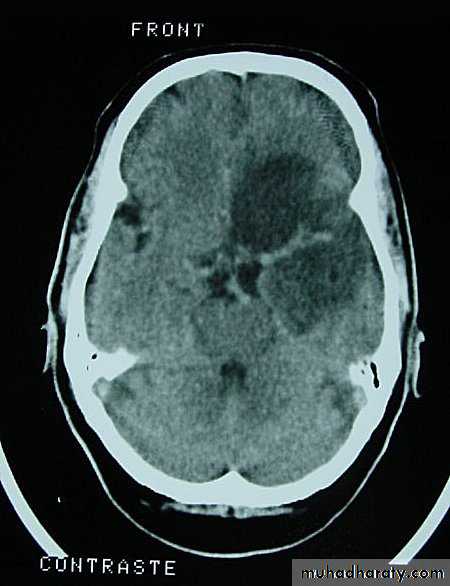

Metastatic Brain Tumours Pre contrast CT

Neurosurgery

Metastatic Brain Tumours Post contrast CT